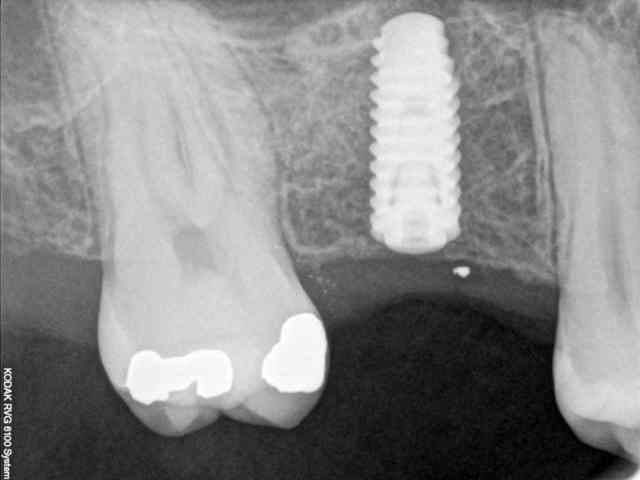

quasiment 6 mois entre les deux interventions (sinus lift et mise à jour)

c'est surtout la qualité des trabéculations osseuses qui m'interpelle.

d'habitude, on voit toujours un peu de particules, ici, c'est vraiment top.

une toute petite remarque, le point blanc sur la radio avec pilier de cicatrisation.

tu as raison, mais on le voit dés les premières radios post extraction.

j'en déduis donc que j'ai bossé comme un cochon pendant cet acte et qu'une inclusion (amalgame ?) est restée dans la gencive.

je crois que c'est la première fois que je vois une cliché radio à quelques mois post-op avec ce matériau et le résultat semble excellent.